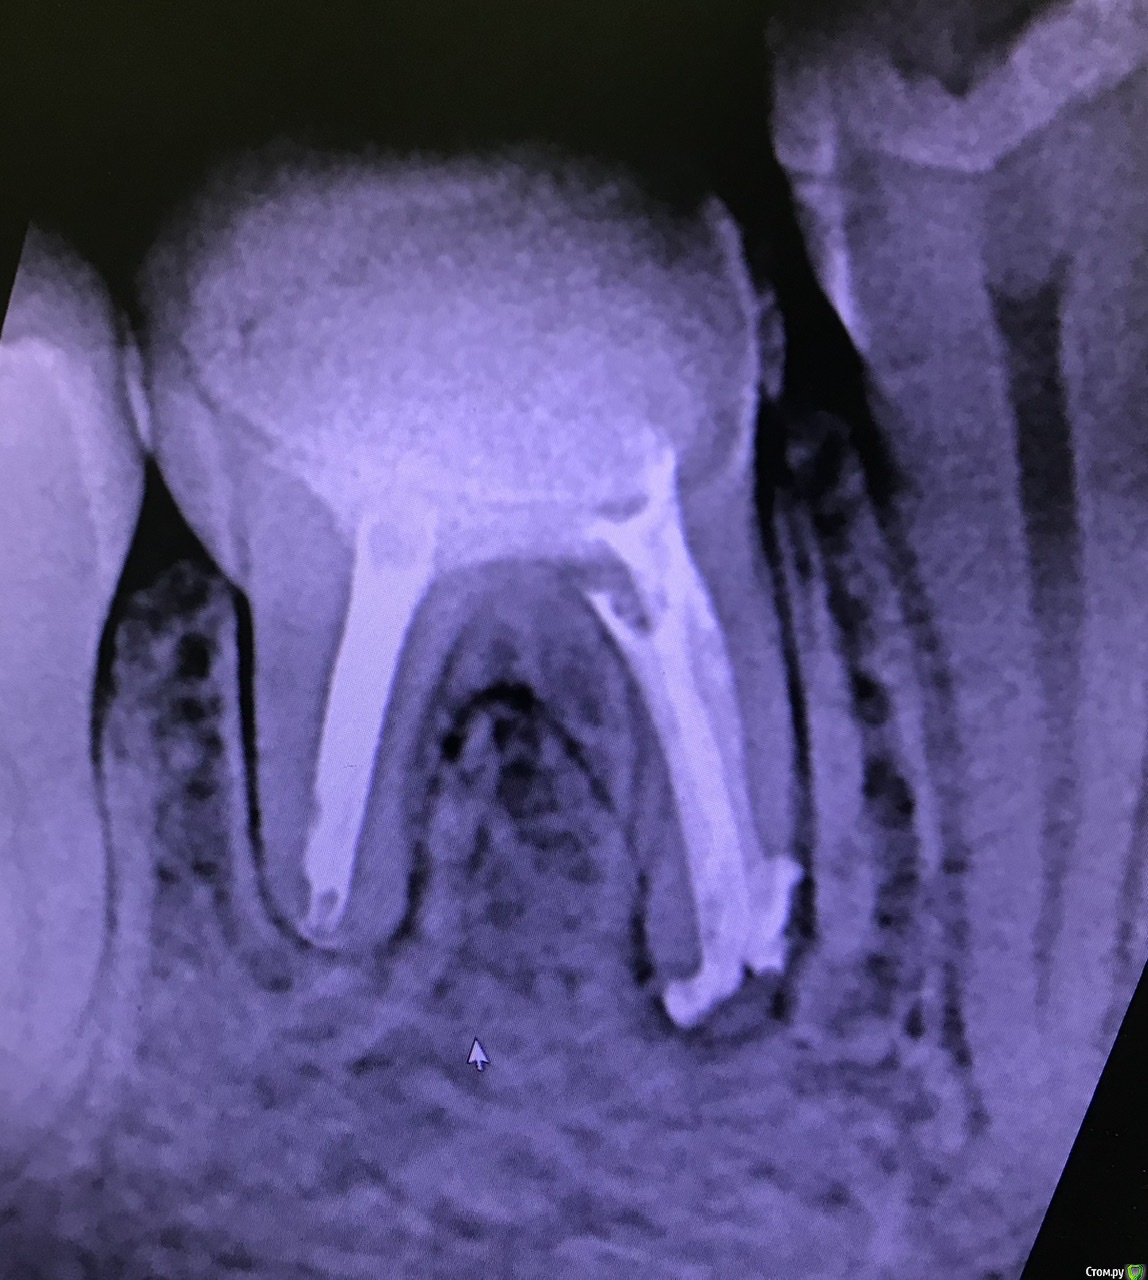

MargaritaEdikovna Опубликовано 22 мая, 2020 Поделиться Опубликовано 22 мая, 2020 (изменено) Здравствуйте, дорогие специалисты!Что вы можете сказать по перелечиванию каналов с кистой на 46 зубе? Правильно ли пролечили?Потому что после установки гуттаперчивых штифтов и постоянной пломбы начались непонятные боли, иногда слабо стреляющие, иногда ноющие, но как будто это десна ноют, иногда как будто распирающие, что хочется его вырвать.Буду благодарна за любые ответы. Изменено 22 мая, 2020 пользователем MargaritaEdikovna 1 Ссылка на комментарий

MargaritaEdikovna Опубликовано 25 мая, 2020 Автор Поделиться Опубликовано 25 мая, 2020 (изменено) Добрый день. После лечения допустим дискомфорт, он постепенно уменьшается и проходит сам по себе. Обычно это несколько дней, но индивидуально может быть и несколько недель. Если же боль со временем не уменьшается или усиливается - нужно показаться своему доктору. Здравствуйте!Доктор говорит, что не знает что болит. Поэтому уже пришлось спрашивать на форуме... При этом я поняла, что боли проявляются такие, как были до лечения. Вот так зуб выглядел до лечения.https://mail.google.com/mail/u/0?ui=2&ik=b2988d84c1&attid=0.1.1&permmsgid=msg-f:1667659142757877677&th=1724b7279a8407ad&view=fimg&sz=s0-l75-ft&attbid=ANGjdJ-QJgKWtcNUCf5zfGscvhc7Amk3aDvF1Yqk1zvwnsxMJgaZJCA2q93AUbnlGDVIvcuu0EEnmFmAcOhvEGSOVn7CKShDuBguQXSLTucTKUIA1ziuP8bS3TDmXr4&disp=emb Изменено 25 мая, 2020 пользователем MargaritaEdikovna Ссылка на комментарий